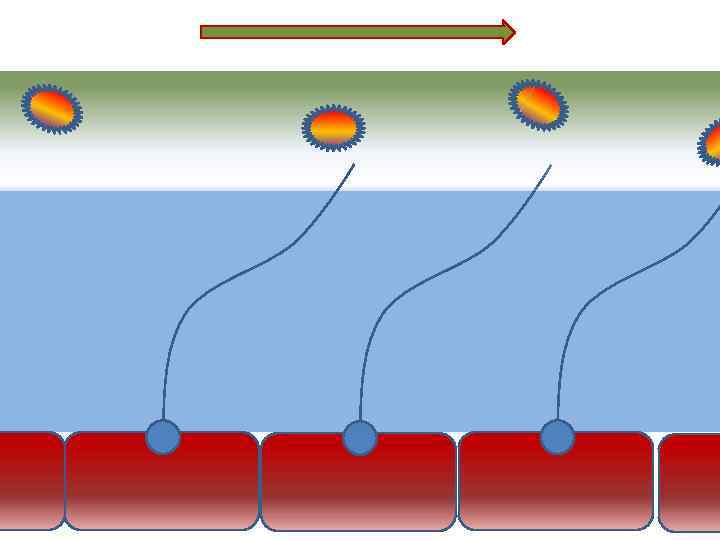

Факторы риска Недостаточное увлажнение дыхательной смеси • естественное удаление бактерий • состояние эпителия трахеи и бронхов

Факторы риска Недостаточное увлажнение дыхательной смеси • естественное удаление бактерий • состояние эпителия трахеи и бронхов

Оптимальное увлажнение 37°С, 44 мг/л Оптимальная влажность • Уменьшает время нахождения патогенной флоры в легком

Оптимальное увлажнение 37°С, 44 мг/л Оптимальная влажность • Уменьшает время нахождения патогенной флоры в легком

Механизм защиты легкого Слизь (зеленый цвет) нейтрализует и связывает патогенную флору(синий цвет) Слизь – это барьер между клетками и патогенной флорой Слизь – это транспортное средство

Механизм защиты легкого Слизь (зеленый цвет) нейтрализует и связывает патогенную флору(синий цвет) Слизь – это барьер между клетками и патогенной флорой Слизь – это транспортное средство

Плохое увлажнение • Вязкая слизь - потеря ресничек • Высушивание слизистой смерть клеток • Высушивание слизи в бронхиолах-ателектазы • Затраты энергии на согревание воздуха • Затраты воды на увлажнение

Плохое увлажнение • Вязкая слизь - потеря ресничек • Высушивание слизистой смерть клеток • Высушивание слизи в бронхиолах-ателектазы • Затраты энергии на согревание воздуха • Затраты воды на увлажнение